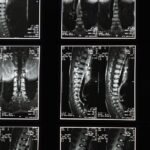

Le domaine de la chirurgie de la colonne vertébrale bénéficie d’avancées technologiques significatives qui améliorent la précision et les résultats des interventions. Parmi ces technologies, la navigation assistée par ordinateur permet aux chirurgiens de visualiser les structures anatomiques en temps réel, optimisant ainsi leur approche. Les systèmes de chirurgie robotique, quant à eux, facilitent le placement précis de vis et d’implants, réduisant les risques et améliorant la stabilité. La réalité augmentée enrichit l’expérience chirurgicale en superposant les données patient sur le champ opératoire, ce qui aide à prendre des décisions éclairées. Avec l’essor de ces innovations, le traitement des troubles de la colonne vertébrale devient plus efficace, offrant aux patients des temps de récupération plus courts et des résultats améliorés.

Les techniques d’imagerie avancée, telles que les scanners 3D et l’imagerie par résonance magnétique (IRM), améliorent la visualisation des structures vertébrales. Cela aide les praticiens à poser des diagnostics plus précis. Ainsi, ils peuvent mieux planifier les interventions et réduire les risques potentiels.

La navigation assistée par ordinateur est une technologie qui permet aux chirurgiens d’effectuer des interventions sur la colonne vertébrale avec une précision accrue. Ce système repose sur l’analyse d’images préopératoires telles que les tomodensitogrammes et les IRM, qui sont transférées dans un logiciel de navigation. Pendant l’opération, le système fournit des informations en temps réel, permettant au chirurgien de visualiser précisément la structure vertébrale et de prendre des décisions éclairées.

Cette approche minimise les risques de complications et améliore les résultats chirurgicaux. Grâce à la navigation assistée, il devient possible de réduire les traumatismes au tissu environnant, ce qui contribue à une diminution significative des délais de récupération post-opératoire.